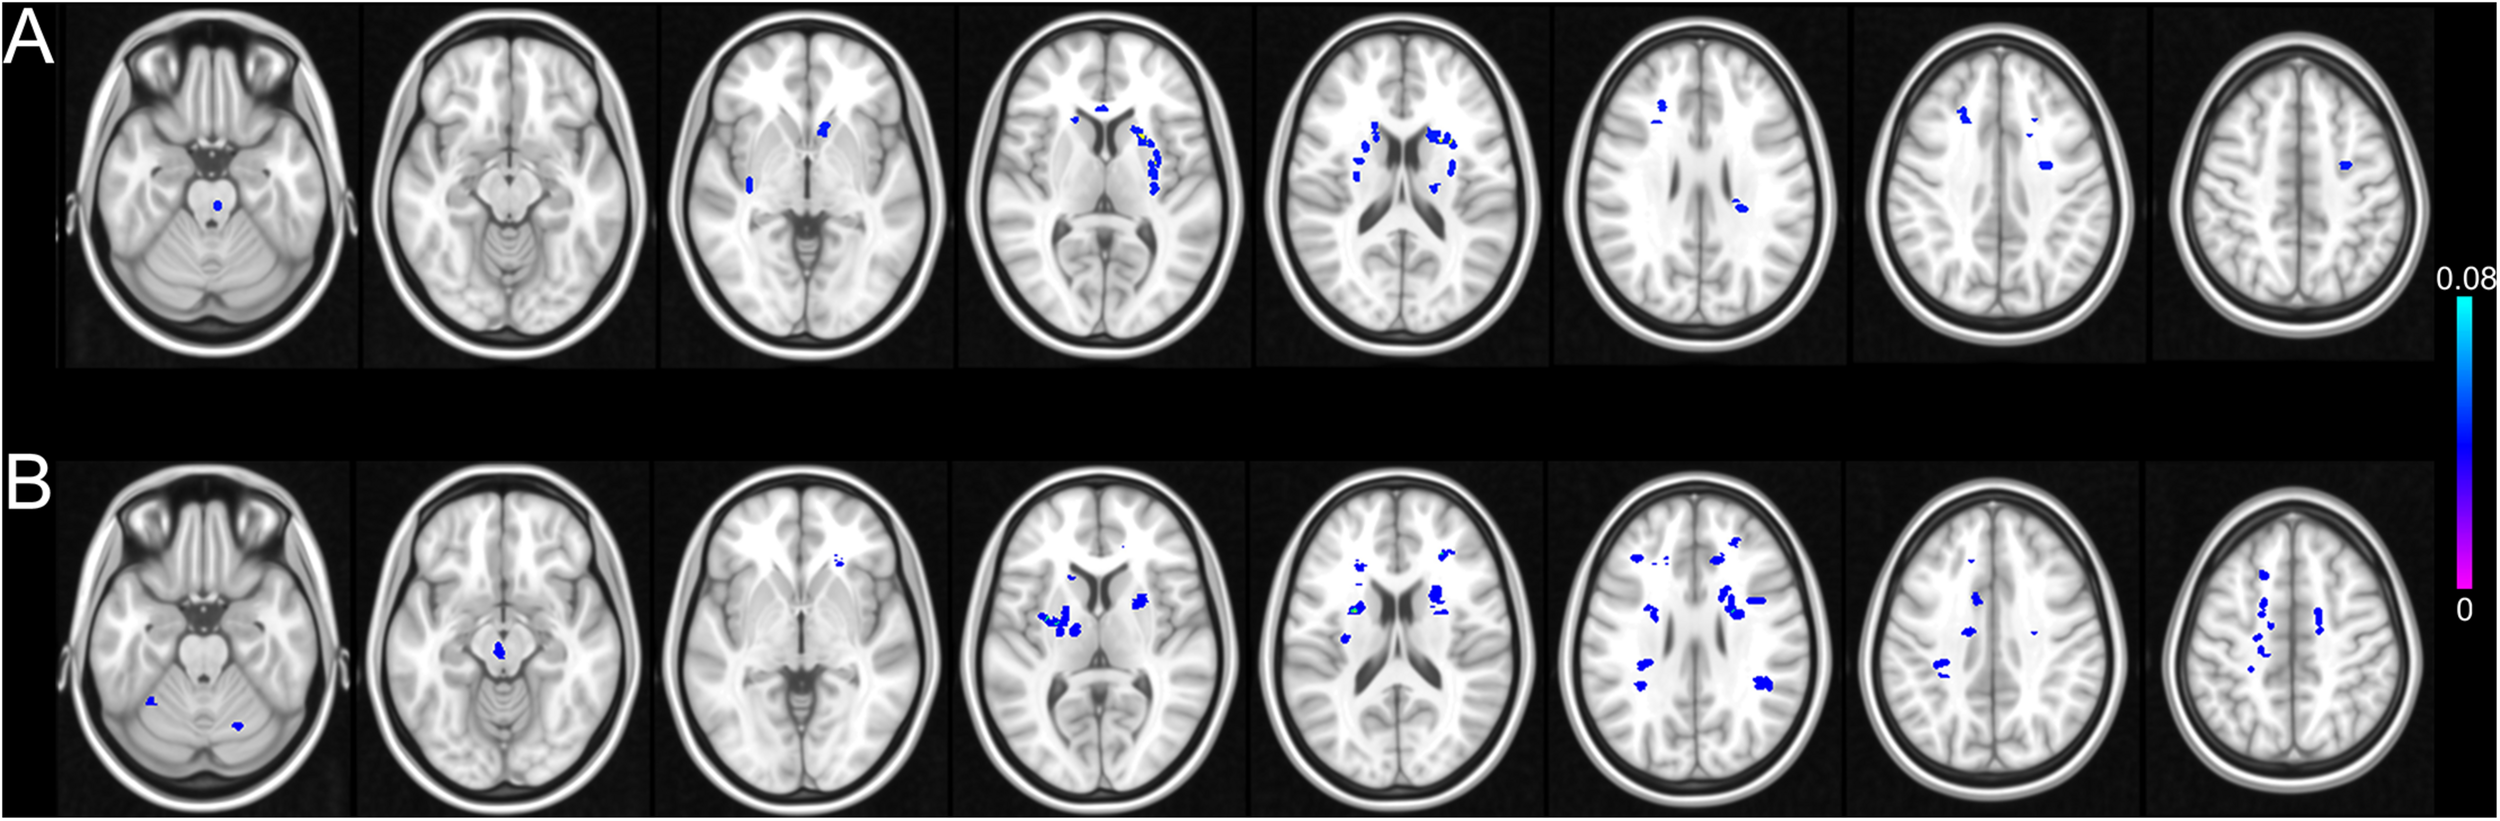

FIGURE 3

Possibility map of WMH in CSVD-NC group and CSVD-MCI group. The WMH are mainly distributed in the periventricular WM, deep WM of bilateral frontal and parietal lobes in both the CSVD-NC group (A) and the CSVD-MCI group (B). Compared with the CSVD-NC group, the lesion load of WMH is increased in the frontal and parietal system in the CSVD-MCI group.

FIGURE 4

Possibility map of lacunar infarcts in CSVD-NC group and CSVD-MCI group. The lacunar infarcts are mainly distributed in the bilateral basal ganglia, deep WM of frontal and parietal lobes in both the CSVD-NC group (A) and the CSVD-MCI group (B). Compared with the CSVD-NC group, the lesion load of lacunar infarcts is increased in the frontal and parietal system in the CSVD-MCI group.

It is interesting to note that, though the CSVD patients were enrolled into the study successively and then classified into the CSVD-NC group and CSVD-MCI group based on the cognitive assessments, the volumes of lacunar infarcts and WMH of the CSVD-MCI group were significantly larger than that of the CSVD-NC group (Figures 2A,B). The distributions of the WMH and lacunar infarcts of the CSVD patients were shown in Figures 3, 4 respectively. In both the CSVD-NC group and the CSVD-MCI group, the distribution of WMH and lacunar infarcts was similar. But the lesion load of WMH and lacunar infarcts was increased in the frontal and parietal system in the CSVD-MCI group compared with the CSVD-NC group. The relative brain volume of the CSVD-MCI group was significantly smaller than that of the control group (P < 0.05) (Figure 2C).